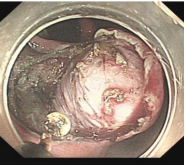

消化道早癌的病例展示(经内镜手术或活检证实):

胃窦印戒细胞癌

十二指肠降段早癌